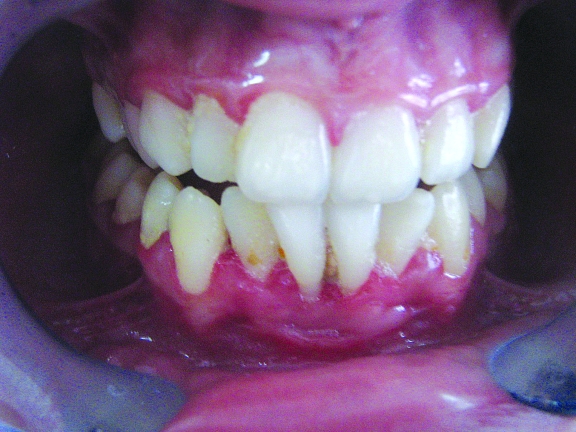

Healing was uneventful. At 4 weeks, her plaque control was not good and the gingiva at the surgical site was edematous and reddish (Figure 3). Normal appearance was established at 4 months postoperatively and the amount of attached gingiva was approximately 3 mm. (Figure 4). At 12 months postoperatively, probing depth at the midbuccal site was less than 1 mm, and the free gingival margin was located less than 0.5 mm apically to the CEJ (Figure 5).

Figure 3.

Clinical view at 4 weeks post-surgery. The surgical site is still edematous and reddish.